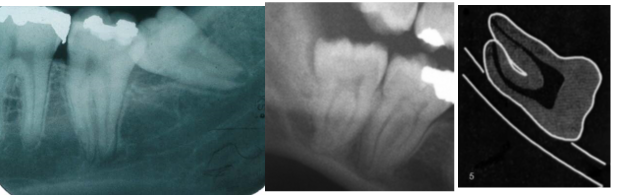

13

Q

what is this

A

diversion/deflection of the inferior dental canal

IDB canal shapes round the outline of the 8 apices

14

darkening of the root where crossed by the canal

Dark band is IDB canal - apices at same level as IDB canal

15

interruption of the white lines/lamina dura of the canal

can usually see both upper and lower borders of IDB canal

but either upper or upper and lower borders of tramline lost

16

deflection of roots

IDB canal caused curvey roots

17

narrowing of inferior dental canal

narrower as it spasses apices of 8